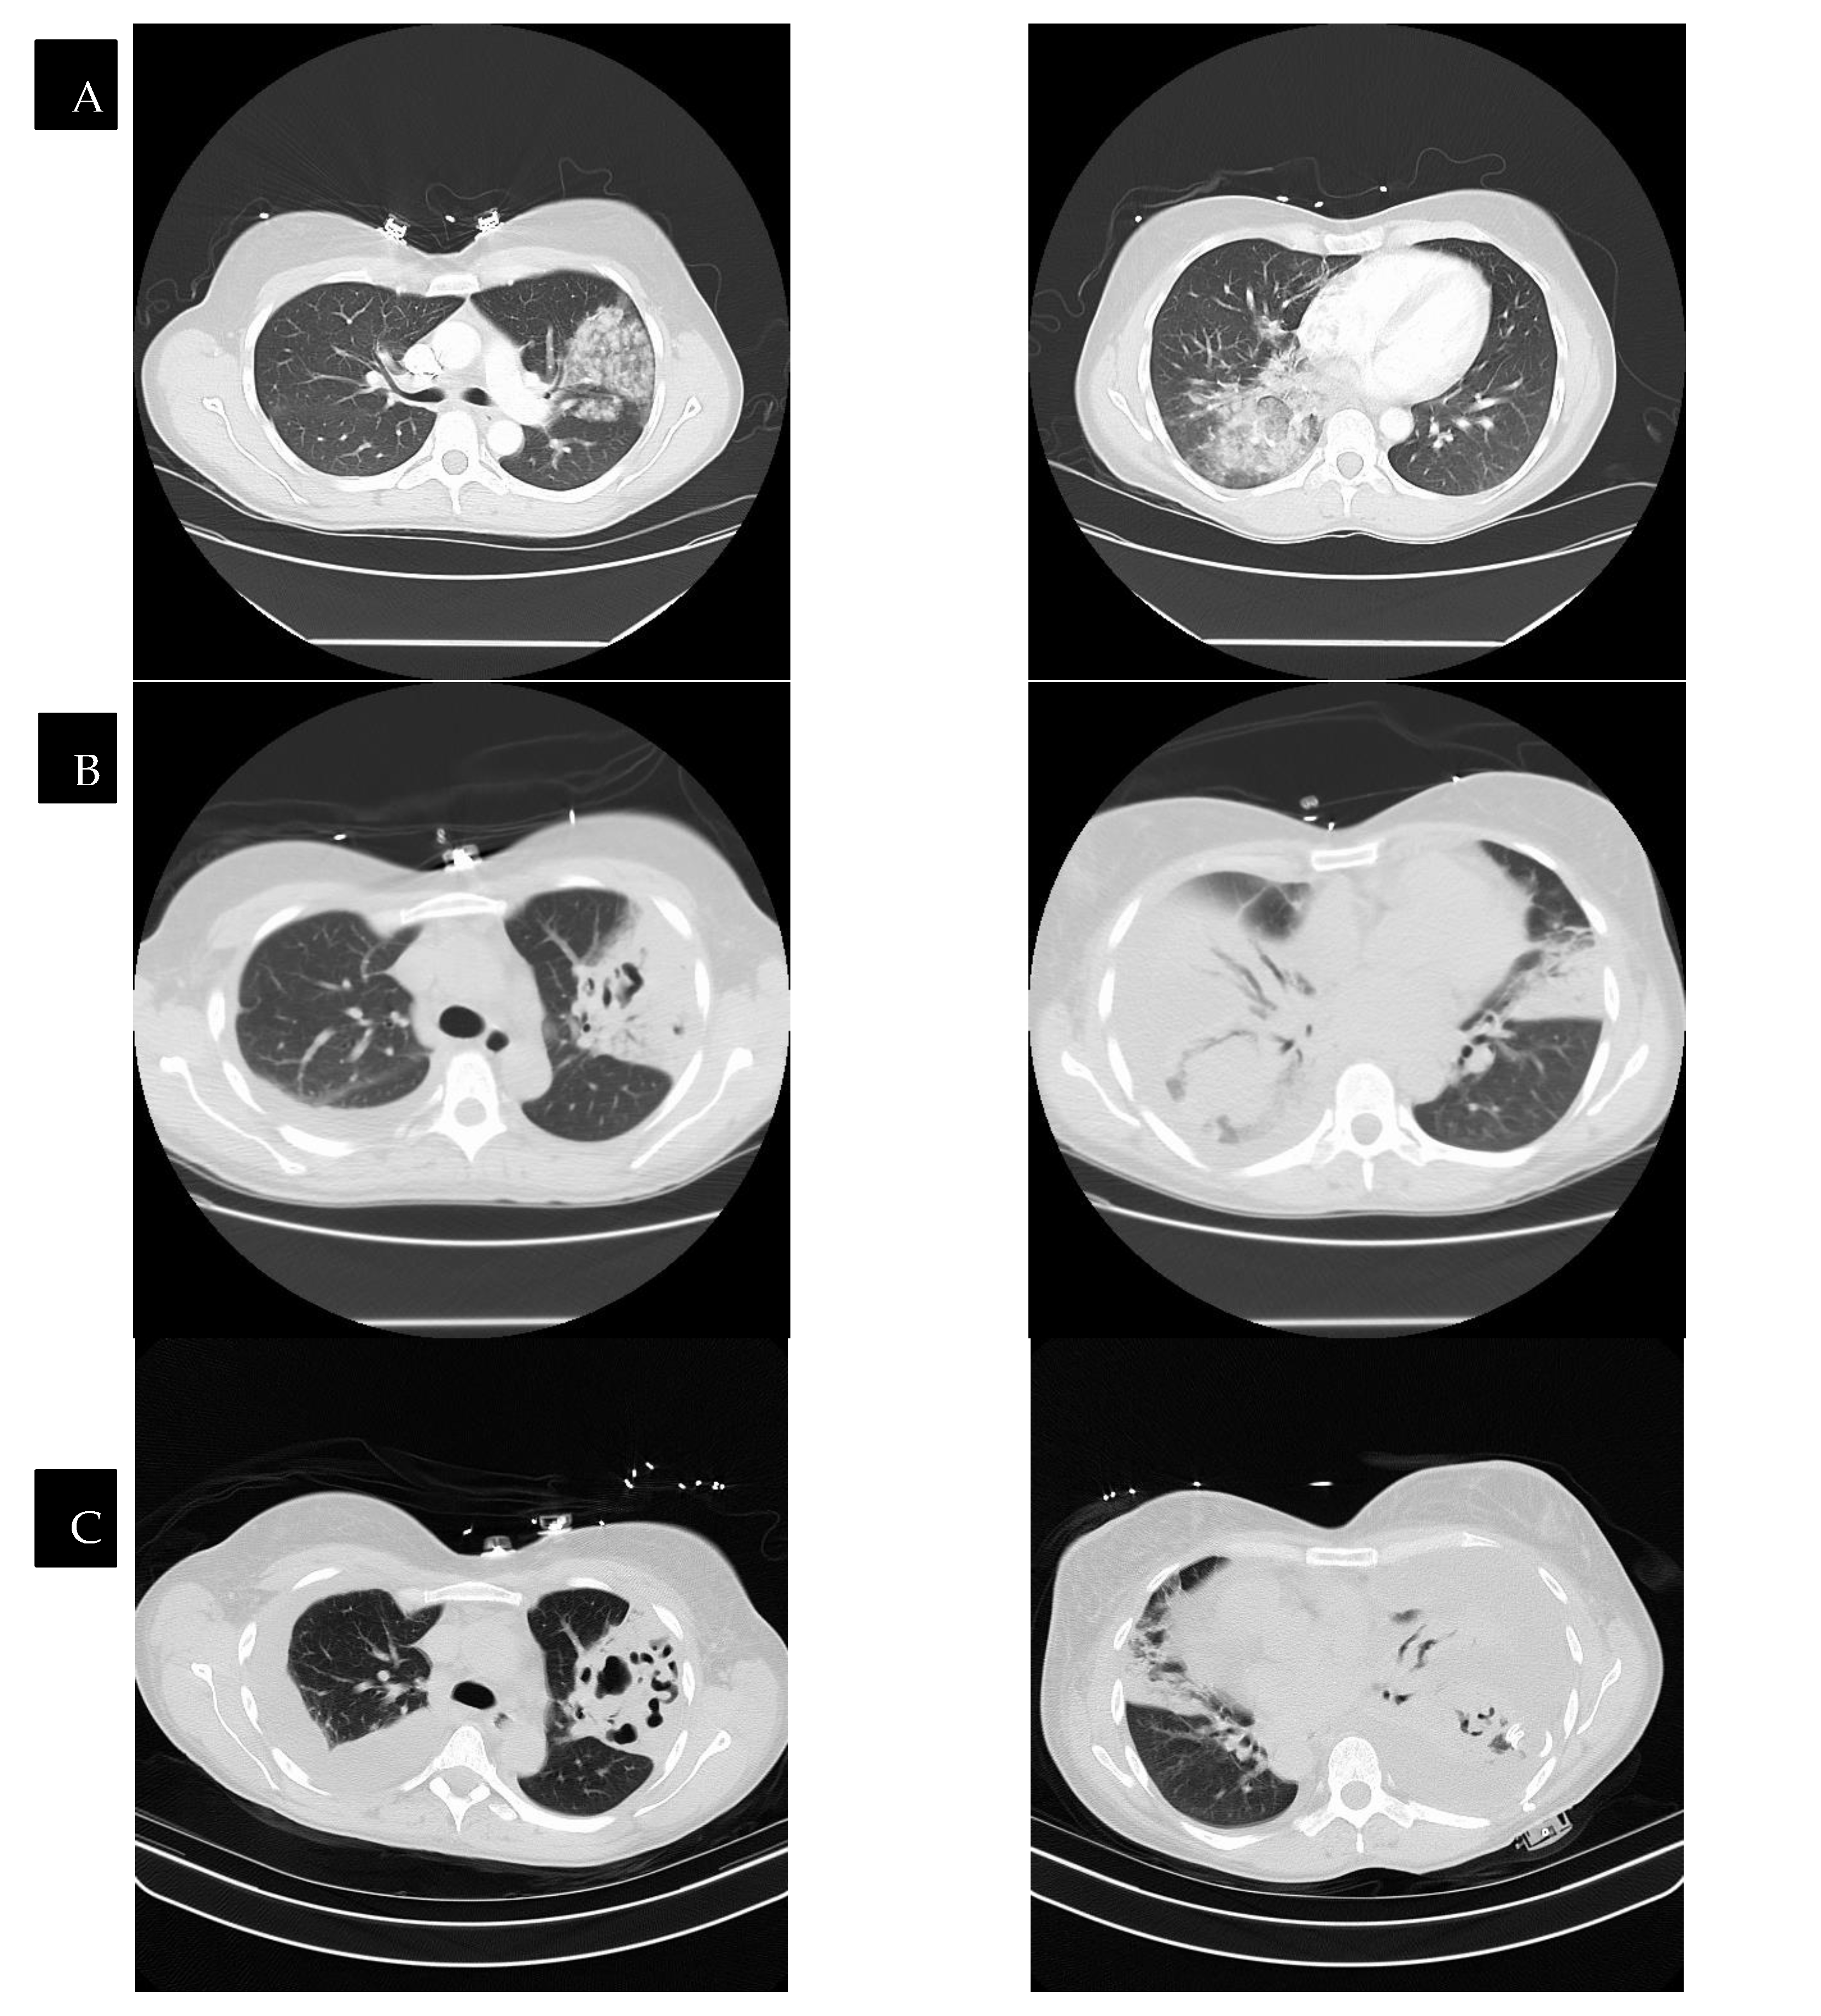

Radiological findings continue to be a mainstay in the diagnosis of necrotizing pneumonia. However, chest X-rays often are not sensitive enough to make the definitive diagnosis of necrotizing pneumonia or to differentiate it from other causes, such as lung abscesses. Bulging fissures may be an early radiographical sign, indicating the extensive inflammation that occurs [3]. A CT with contrast is the optimal imaging modality as it enables the appreciation of areas with low attenuation and decreased enhancement, which are compatible with necrotizing lesions. In contrast to pulmonary abscesses or gangrene, which tend to be isolated to one lobe, necrotizing pneumonia more frequently is multi-lobar in nature and has more extensive airway disease [3,17]. The right middle and lower lobes are most commonly affected in imaging [25]. The presence of micro-abscesses can be used to distinguish necrotizing pneumonia from other conditions causing parenchymal lucency. Significant overlap continues to exist between radiographical findings of necrotizing pneumonia and pulmonary gangrene. Many sources use the extent of lobe involvement as a distinguishing feature, with the term pulmonary gangrene being used when greater than 50% of the lobe is affected [26]. (See Figure 2).

Figure 2.

CT scans of a patient with necrotizing pneumonia and progression through time, with row (D) representing images after the completion of treatment. The time between images in row (A) and row (D) is six weeks. Row (B,C) represent CTs that were taken in between the time of row (A) and row (D), showing the progression of improvement.